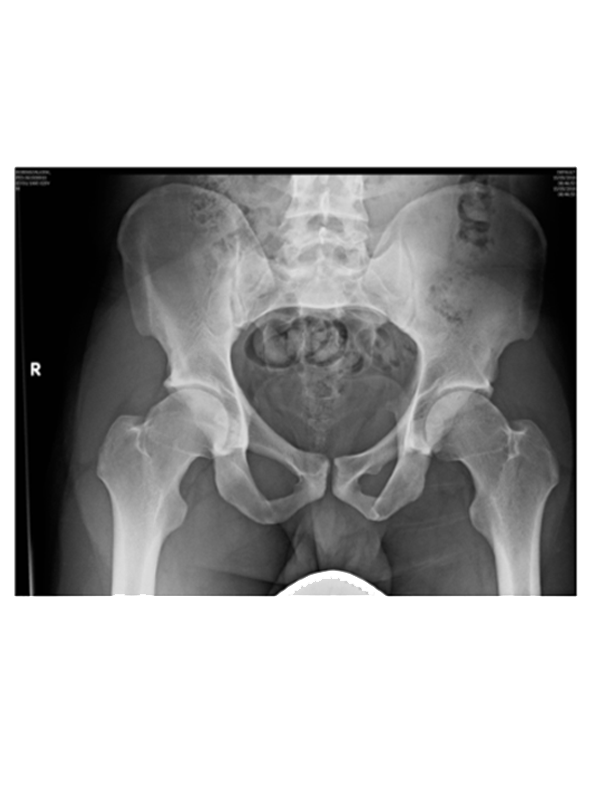

Types of Imaging

Imaging refers to technologies used to view the human body for diagnostic and treatment purposes. These include the following methods:

- XRAY

XRAY tells us the most information in hip diagnosis. It can determine Arthritis, Dysplasia, Impingement, and Fractures.